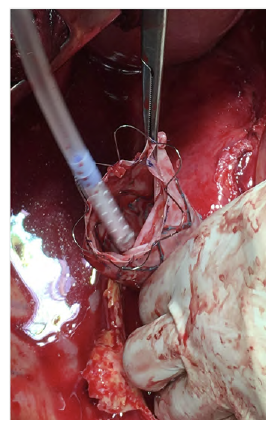

After a multidisciplinary discussion, a staged approach was decided. The first step aimed for oesophagus defunctionalization, by performing cervical oesophagus stapling, a drainage gastrostomy, and a feeding jejunostomy. After a two-week course of broad-spectrum antibiotics and antimycotics the patient underwent the definitive surgical treatment. A left lateral thoracotomy was performed, exposing the descending aorta and the oesophageal fistula (Figure 2). The stent graft was explanted (Figure 3), extensive debridement was followed by in situ reconstruction of the descending aorta with an aortic interposition of a silver and Triclosan impregnated Dacron graft (Figure 4), and lastly by esophagectomy (Figure 5), and eosophagogastrostomy (Figure 6). An intercostal muscle flap was used to fill the aortoesophageal space, to cover the graft and to take advantage of its neovascularization potential. The postoperative period elapsed without any major complications and the patient was discharged after 30 days. Antibiotic and antifungal drugs were administrated until discharge.